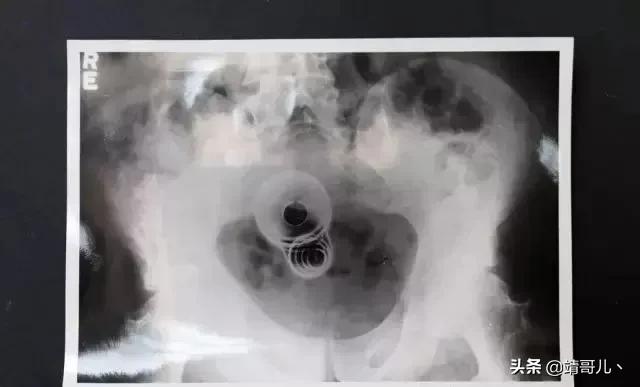

4. 金属铅笔 (1932年)

这是当时有一名46岁的精神病患因为妄想症而做出的猎奇之举:他将金属铅笔从尿道塞入他的膀胱。(我们亲爱的男性读者们,读到这有没有觉得头皮发麻?)

所幸当时已经有X光的技术,才得以完整地取出。后来这名病患也得以痊愈。